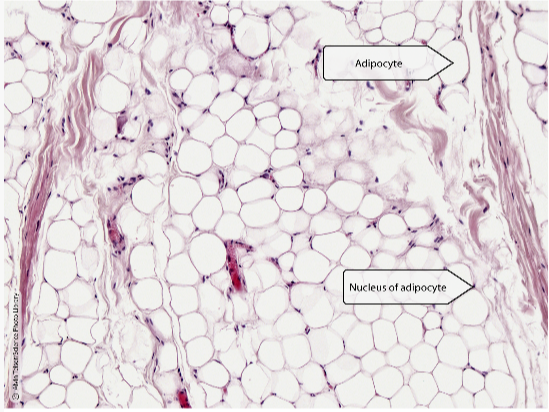

Q

what tissue is this? locate:

- adipocyte

- neucleus of adipocyte

A

loose connective tissue

- adipose tissue